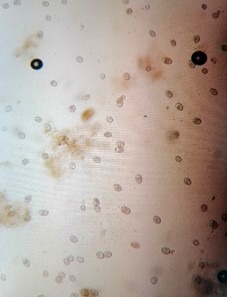

Naš tim za saradnju može da izvrši osnovnu pretragu statusa stada i da odredi vrste parazita i stepen infestacije (zaraženosti). Parazitoze mogu nanositi od blago štetnih efekata do smrtonosnih. Smatra se da su paraziti u mogućnosti da uspore rast i do 30% na nivou stada. Sa druge strane, stajsko čuvanje ovaca često dovodi u zabludu odgajivača da je dehelmintizacija („čišćenje od glista“) obavezna i rutinska, pri čemu se životinje nemaju odakle zaraziti parazitima.

Ovde se pojavljuju drugi problemi intenzivnog ovčarstva u zatvorenom prostoru (u vidu kokcidioza mladih jaganjaca) što treba posebnim programom prevenirati. Takođe, izbor antiparazitika mora biti prema izolovanoj vrsti, a da komplikacija bude i veća, javljaju se i rezistencije na lekove.

Dakle, postoje paraziti koji se mogu detektovati prilikom obdukcije, klanja ali je standardna metoda analiza izmeta.